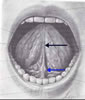

1-Mukoz zardır. Örneğin sindirim kanalını örten zardır.

2-Sindirim borusu, soluk borusu gibi iç organların iç yüzeyini örten ve mukus sıvısı salgılayan ince tabakadır.

Mukus tabaka. Örneğin sindirim kanalını örten zar.